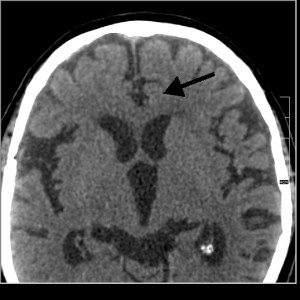

»Nepričakovan šokanten dogodek naprej povzroči tako imenovano lezijo v možganih, in sicer na točno določenem predelu. Gre za prekinitev sinaptičnih povezav, ki so jih kasneje poimenovali Hamerjeve lise ali Hamer-herdi (HH). Če je tak konflikt dovolj močan, se na CT posnetku pokaže kot tarča: jasni prstanasti obroči. Prizadete možganske celice pošljejo električne in biokemične impulze v njim pripadajoči predel telesa in s tem povzročijo rast tumorja, propad tkiva ali prekinitev delovanja. Kaj konkretno, pa je odvisno od tega, v katerem predelu možganov je središče kratkega stika. Skozi evolucijo so bili možganski predeli programirani, da se ustrezno odzovejo v primeru konflikta, ki bi lahko ogrozil preživetje. Zato so posamezne vrste konfliktov povezane s točno določenimi predeli v možganih, kar je dr. Hamer tudi topografsko kartiral,« pravi Varga.

Tisti trenutek, ko doživimo čustveni odklon ali travmo, pride v možganih do lezije – prekinitve sinaptičnih povezav. To je začetek »smiselnega biološkega superprograma« ter se da ugotoviti in videti na CT posnetkih glave. Lezije se spreminjajo ves čas trajanja smiselnega biološkega superprograma, ob koncu pa ostane brazgotina, ki jo je bolj ali manj možno ugotoviti vse do konca življenja. Dr. Hamer, ki je to odkril, je bil pravi fenomen v »branju« takih CT posnetkov. Pred njim ni bilo skrito čisto nič.

CT glave 84-letnega desničarja

Bele puščice kažejo na stare brazgotine - ostanke konfliktov in lezij iz preteklosti. Ti so sedaj že neaktivni. Smiselni biološki superprogrami so se iztekli. Črna puščica je na releju desnega srednjega ušesa in kaže na aktivni konflikt. Čustvena vsebina biološkega konflikta je želja po »zalogaju« glasu ali »Želel bi slišati, manjkajo mi … glasovi, besede, pogovor. Brez teh glasov je življenje prazno.«